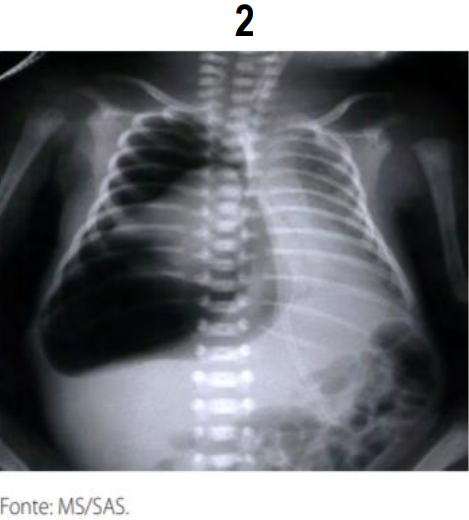

A radiografia de tórax é o exame de eleição para o diagnóstico das várias formas de SEAr. É fundamental, também, para a determinação do tamanho e da extensão da coleção de ar e da coexistência de outras entidades que possam facilitar ou perpetuar o escape de ar, além de permitir o acompanhamento evolutivo e avaliar a eficácia da terapêutica adotada. Na grande maioria dos casos o aspecto radiológico é típico, sendo possível definir o diagnóstico com relativa facilidade. Analise as imagens radiológicas com sinais patognomônico e assinale a alternativa da doença associada